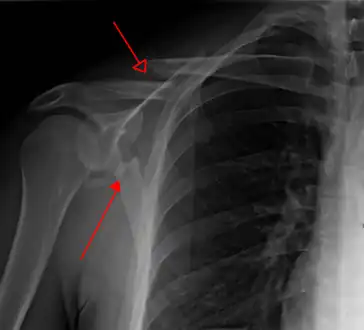

X-ray showing a fracture of the clavicula and scapula